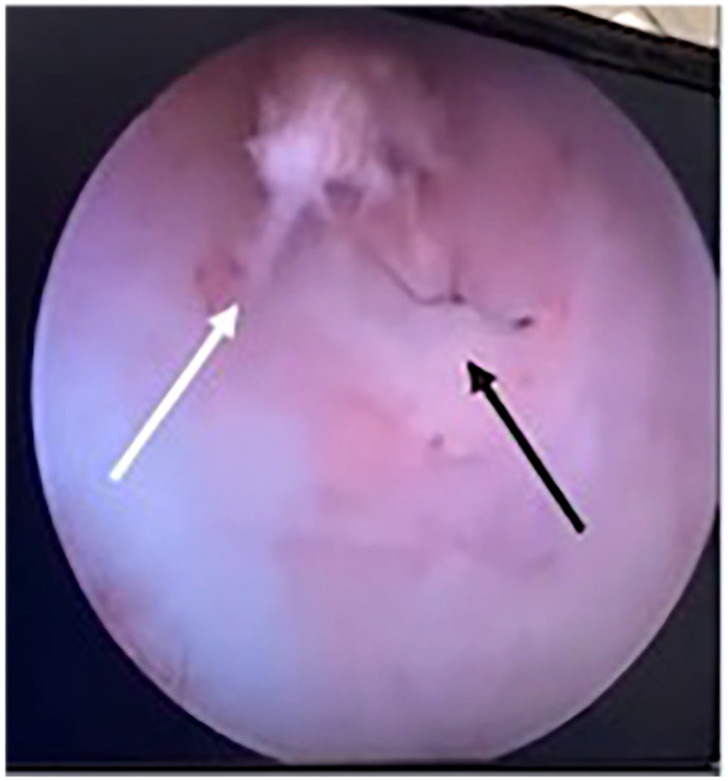

Case summary: A 2-year-old domestic shorthair queen sustained a tear in the vaginal wall through which the queen herniated a fetus during parturition. An exploratory laparotomy was performed, the patient had an ovariohysterectomy and the fetus was removed vaginally. The tear was managed medically with antibiotics, analgesics and careful monitoring. Assessment of the injury site 2 weeks later confirmed successful healing without the need for surgical intervention in the vaginal wall.

Relevance and novel information: This is the first report in veterinary medicine describing the successful medical management of a dystocia-related vaginal wall tear in a feline patient without surgical repair.